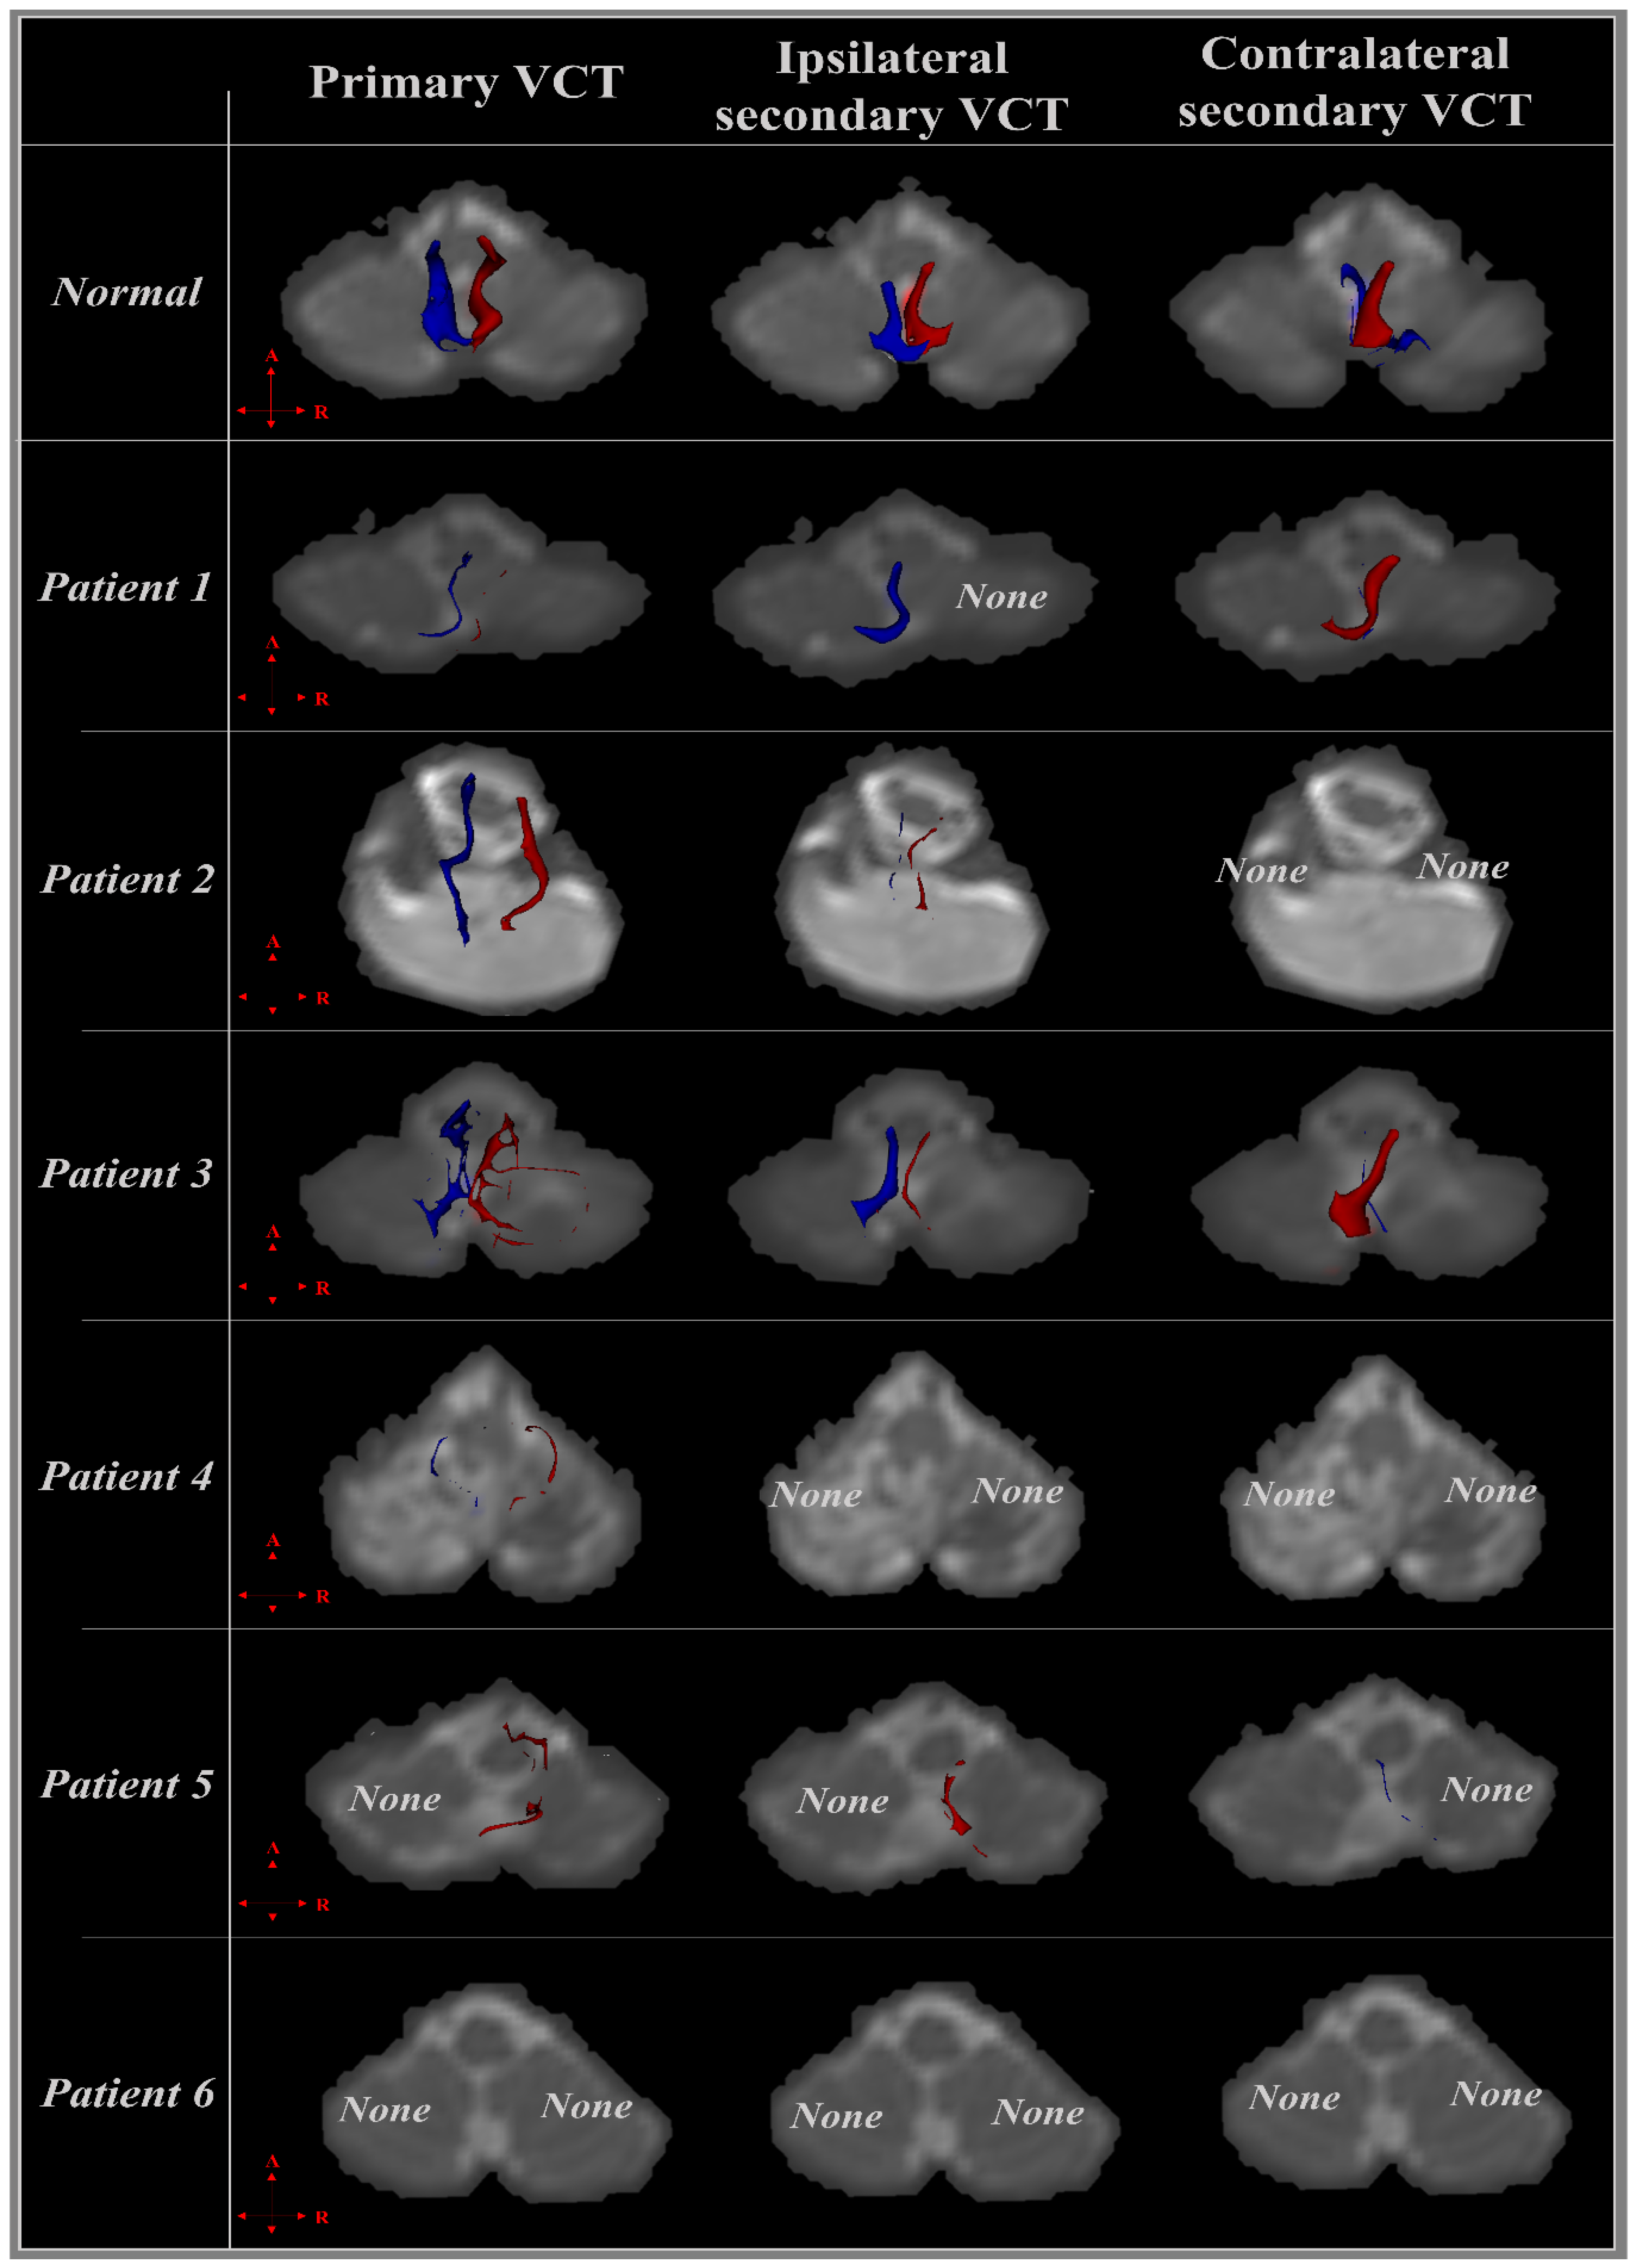

3.2. Diffusion Tensor Imaging

3.2.1. Patient 1

3.2.2. Patient 2

3.2.3. Patient 3

3.2.4. Patient 4

3.2.5. Patient 5

3.2.6. Patient 6

| Patient | CST | Primary VCT | Ipsilateral Secondary VCT | Contralateral Secondary VCT | |

|---|---|---|---|---|---|

| 1 | R | + | + | − | + |

| L | + | + | + | + | |

| 2 | R | + | + | − | − |

| L | + | + | − | − | |

| 3 | R | + | + | + | − |

| L | + | − | − | + | |

| 4 | R | + | + | + | − |

| L | + | + | + | − | |

| 5 | R | + | + | + | + |

| 6 | R | + | − | − | − |

| L | + | − | − | − | |

| Injury rate (%) | 0.00 | 25.00 | 50.00 | 58.33 | |